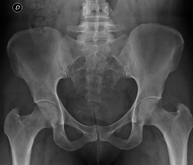

- RX Pelvis

Procedimiento mediante el cual, utilizando rayos X, se obtienen imágenes de la pelvis para su estudio, especialmente de los huesos pélvicos.

- RX Caderas pediatría

Estudio que, utilizando los rayos X, permite obtener una imagen de los huesos de la cadera y descartar luxaciones.

- RX Caderas